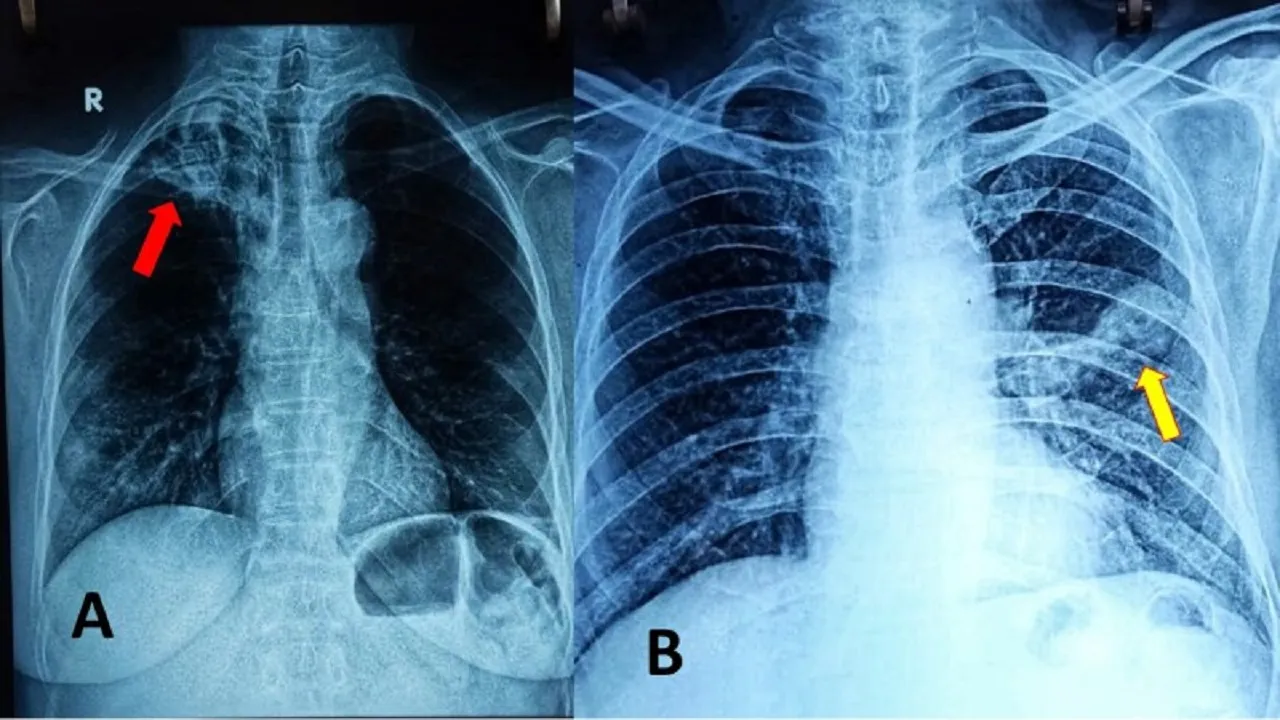

ಈ ಜೋಡಿ ಆಕ್ರಮಣವು ಕಾಕತಾಳೀಯ ಎನ್ನುವುದಕ್ಕಿಂತ ಹೆಚ್ಚಿನ ವಿಷಯವಾಗಿದೆ. ಇದು ಸಿಂಡೆಟಿಕ್ ಸ್ಥಿತಿಯ ಒಂದು ಶ್ರೇಷ್ಠ ನಿದರ್ಶನವಾಗಿದೆ, ಇಲ್ಲಿ ಎರಡು ರೋಗಗಳ ಅಂತರ್‌ಕ್ರಿಯೆ ಯಿಂದಾಗಿ ಉಭಯ ರೋಗಗಳ ಪ್ರಭಾವ ಹೆಚ್ಚಾಗಿ ರೋಗಿಯ ಪರಿಸ್ಥಿತಿಯನ್ನು ಹದಗೆಡಿಸುತ್ತದೆ. ಮೈಕೋಬ್ಯಾಕ್ಟೀರಿಯಂ ಟ್ಯೂಬರ್‌ಕ್ಯುಲೋಸಿಸ್ ಎಂಬ ಬ್ಯಾಕ್ಟೀರಿಯದಿಂದ ಉಂಟಾಗುವ ಟಿಬಿ (ಕ್ಷಯರೋಗ), ಗಾಳಿಯ ಮೂಲಕ ಹರಡುತ್ತದೆ. ಅಲ್ಲದೇ ಪ್ರಾಥಮಿಕವಾಗಿ ಶ್ವಾಸಕೋಶದ ಮೇಲೆ ಪರಿಣಾಮ ಬೀರುತ್ತದೆ. ಜೊತೆಗೆ ಇದು ಇತರ ಅಂಗಗಳಿಗೆ ಹಾನಿ ಮಾಡಬಹುದು. ಇನ್ಸುಲಿನ್ ಪ್ರತಿರೋಧ ಅಥವಾ ಕೊರತೆಯಿಂದಾಗಿ ಸತತ ಉನ್ನತ ಪ್ರಮಾಣದ ರಕ್ತದ ಸಕ್ಕರೆಯಿಂದ ಗುರುತಿಸ ಲಾಗುವ ಮಧುಮೇಹವು ದೇಹದ ರೋಗ ನಿರೋಧಕ ವ್ಯವಸ್ಥೆಯನ್ನು ದುರ್ಬಲ ಗೊಳಿಸುತ್ತದೆ. ಇದರಿಂದ ದೇಹವು ಟಿಬಿಯಂತಹ ಸೋಂಕುಗಳ ವಿರುದ್ಧ ಹೋರಾಡುವುದು ಕಷ್ಟವಾಗುತ್ತದೆ.

ಭಾರತದ ದ್ವಂದ್ವ ಆರೋಗ್ಯ ಹೊರೆಗಳಿಂದ ಅಪಾಯಗಳು ಹೆಚ್ಚಾಗುತ್ತವೆ. ಕಿಕ್ಕಿರಿದ, ಕಳಪೆ ಗಾಳಿ ಮತ್ತು ಅಪೌಷ್ಟಿಕತೆಯ ವಾತಾವರಣಗಳಲ್ಲಿ ಕ್ಷಯ ರೋಗ ಬೆಳೆಯುತ್ತದೆ. ಆದರೆ ಮಧುಮೇಹವು ಜಡ ಜೀವನಶೈಲಿ, ಹೆಚ್ಚಿನ ಸಂಸ್ಕರಿಸಿದ-ಕಾರ್ಬ್(ಶರ್ಕರ ಪಿಷ್ಟಾದಿ) ಆಹಾರಗಳು, ಬೊಜ್ಜು ಮತ್ತು ಆನುವಂಶಿಕ ಪ್ರವೃತ್ತಿಯಿಂದ ಚಾಲನೆ ಪಡೆಯುತ್ತದೆ. ಕಳಪೆಯಾಗಿ ನಿರ್ವಹಿಸಲಾದ ಮಧು ಮೇಹವು ಕ್ಷಯ ರೋಗಲಕ್ಷಣಗಳನ್ನು ಮರೆಮಾಚಬಹುದು, ರೋಗನಿರ್ಣಯವನ್ನು ವಿಳಂಬ ಗೊಳಿಸಬಹುದು ಮತ್ತು ಸುಪ್ತ ಕ್ಷಯವು ಸಕ್ರಿಯವಾಗುವ ಸಾಧ್ಯತೆಯನ್ನು ಇದು ಹೆಚ್ಚಿಸುತ್ತದೆ.